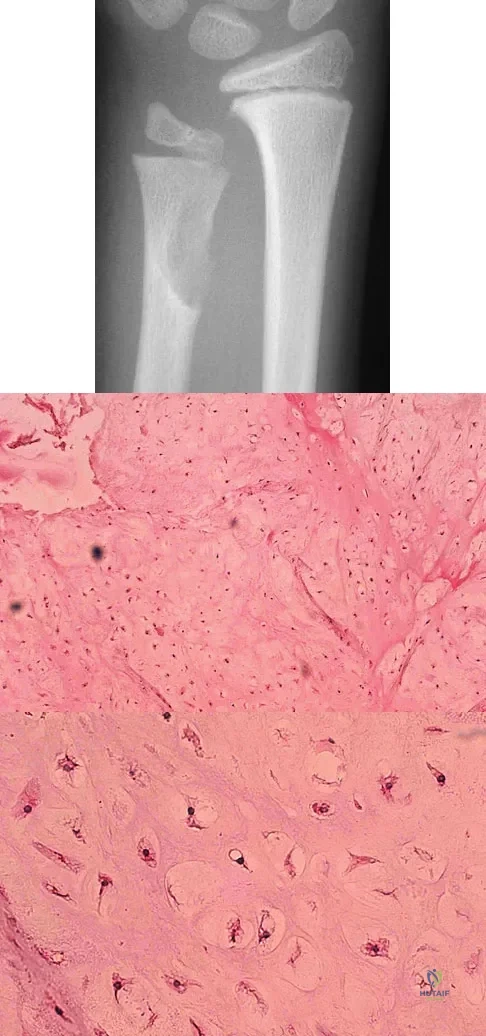

A 10-year-old boy has had wrist pain for the past 3 months. He denies any history of trauma. He reports mild tenderness associated with a palpable mass. A radiograph and biopsy specimens are shown in Figures 52a through 52c. What is the most likely diagnosis?

Explanation